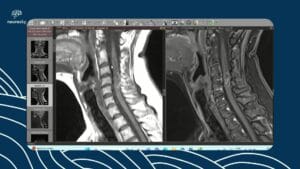

Imagem ponderada em difusão do crânio pode detectar dissecções da artéria carótida interna cervical